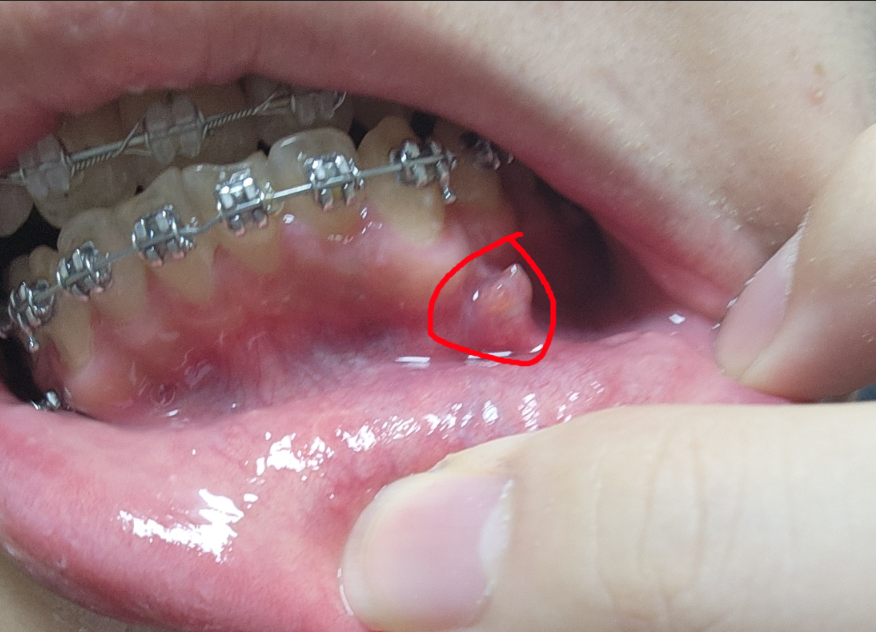

교정 스크류 후.. 잇뫂이 덮었어요..

지금 사진에서 보이듯이 저 돌기같은? 부분에 원래 교정스크류가 삽입되어있었습니다. 그러나 못 보던 사이 몇일 지나니 이렇게 되어있더군요 ㅠㅠㅠ 현재 고통이나 그런건 전혀 없고 잘 가라앉지도 않네요.. 일주일 내로 치과 갈 예정이었는데 더 빨리 가는게 낫겟죠?

스크류 심은곳에 잇몸이 증식되서 그런거 같습니다. 저부위는 간단히 잇몸을 제거하면 해결되는 부분이니 추후에 마취하시고 잇몸을 제거하면 스크류가 다시 노출됩니다.

스크류를 삽입한 부위에 염증이 생겨서 부풀어 오른 것으로 보입니다. 이 경우에는 빠른시일내에 치과에 방문하여 상태를 파악하고 조치를 받길 권합니다.